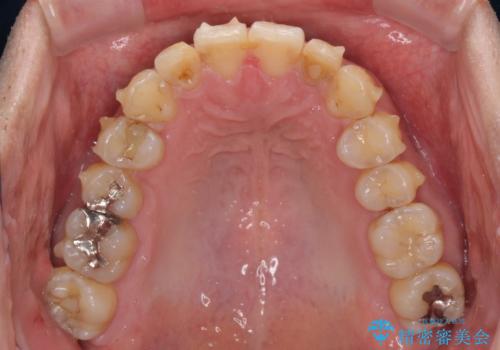

前歯のデコボコと下顎の八重歯 インビザラインによる矯正治療

- 前歯のデコボコや八重歯を気にして来院された患者様です。

インビザラインを用いて、歯列を整えることとしました。